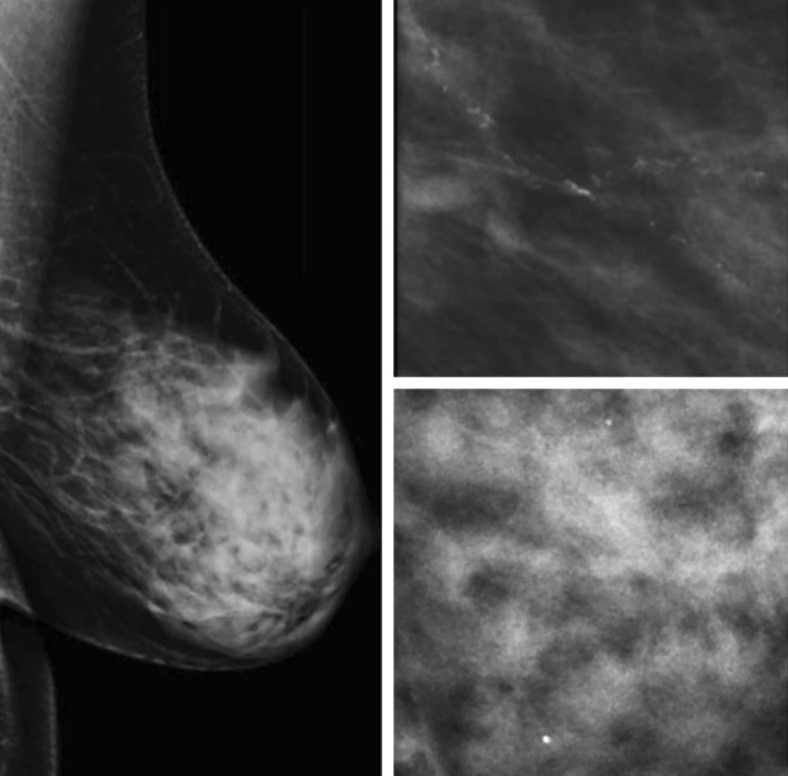

В данном проспективно-ретроспективном исследовании был проведен анализ результатов маммографического исследования 1030 пациенток, проходивших диспансеризацию в Университетской клинике МНОИ МГУ имени М.В.Ломоносова в период с 2019 по 2023 год. Для адекватной трактовки результатов инструментальной диагностики РМЖ была использована система BI-RADS (Breast Imaging Reporting and Data System). Оценка плотности молочных желез проводилась на основании шкалы, разработанной Американским колледжем радиологии (англ. – ACR - American College of Radiology) [9]. Согласно этой шкале, выделяют 4 типа молочных желез (Рис.1):

А – МЖ практически полностью жировой плотности (термин "плотность" здесь и далее в данном контексте характеризует степень ослабления рентгеновского излучения при прохождении через ткань молочной железы). Маммография обладает высокой чувствительностью.

В - Отдельные участки фибро-гландулярной (фиброзно-железистой) низкой рентгенологической плотности.

С - МЖ неоднородной (гетерогенной) высокой плотности, либо отдельные участки молочных желез достаточно плотные и могут скрывать небольшие образования.

D - Очень плотные МЖ. Маммография обладает низкой чувствительностью.